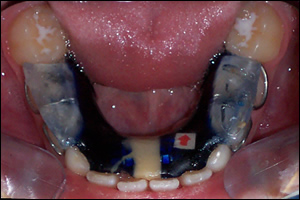

Fig 2: Twin Block appliances were fabricated to open the bite and advance the mandible.

Fig 4: The Maxillary Twin Block

Fig 5: The Mandibular Twin Block